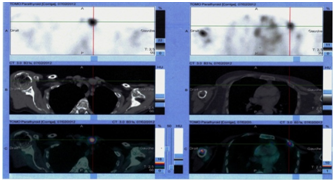

The diagnosis of parathyroid adenoma was highly suspected. The patient was then referred for dabble phase parathyroid scintigraphy. Planar images and hybrid single-photon emission computed tomography-computed tomography (SPECT/CT) was performed after intravenous injection of 555MBq of 99mTc-sestamibi. Planar images showed a large area of pathological uptake of the radiotracer projecting below the lower pole of the left thyroid lobe suggesting an abnormal parathyroid and did not find mediastinal or cervical ectopic gland (Figure 3). The cervico-thoracic SPECT/CT and the fused images beside confirm and localize the left inferior parathyroid adenoma and shows left scapula, right humerus and costal osteolytic lesions (Figure 4). The patient was sent to ORL for surgery. Histology confirmed a parathyroid adenoma. PTH levels decreased considerably after surgery.

Figure 3 Tc99m-sestamibi dabble phase parathyroid scan showing a left inferior parathyroid adenoma.

Figure 4 Tomographic acquisition coupled to a CT-scan of the cervical region showing the left inferior parathyroid adenoma and a left rib brown tumor.